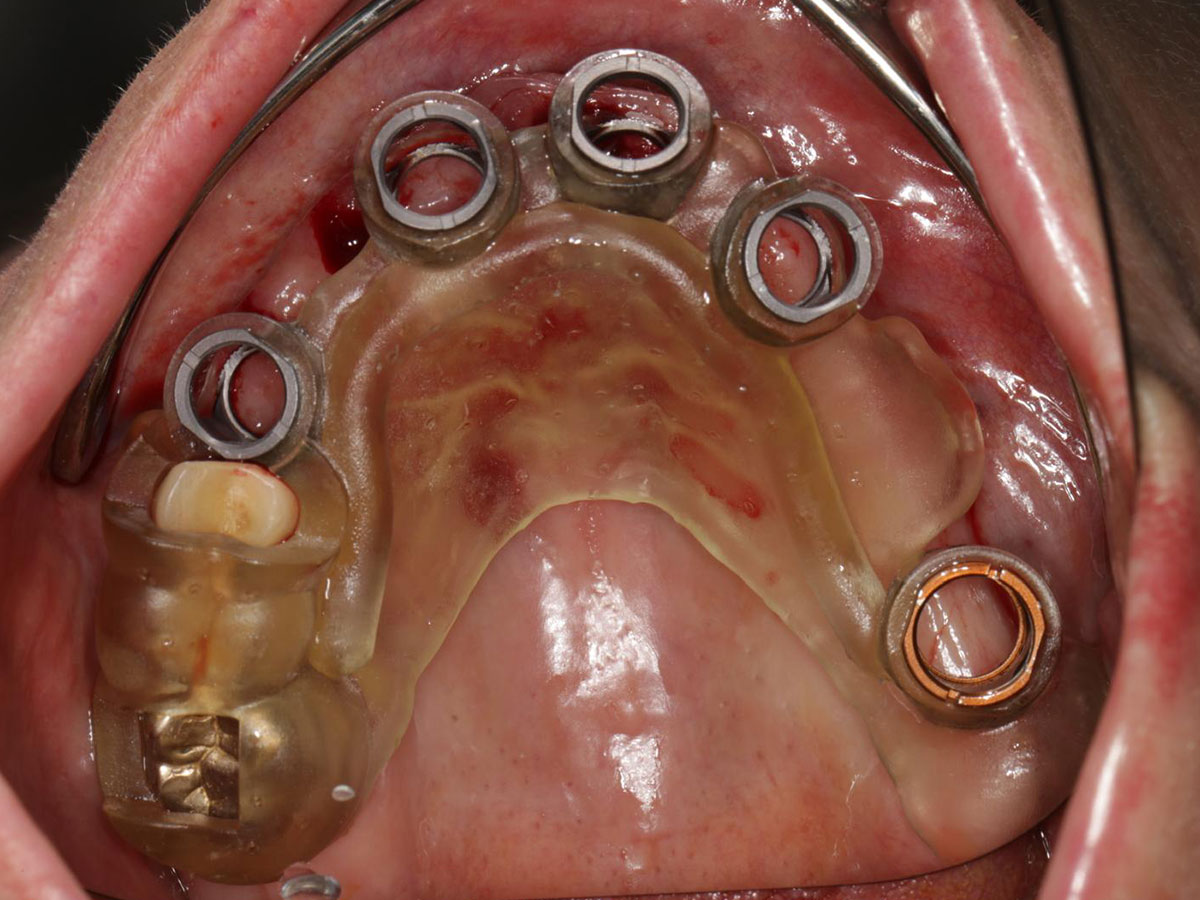

Digitale Planung

· Planungssicherheit durch digitale Simulation

· DVT- und intraorale Scandaten: Erfassung, Matching und Planung

· Virtuelle Implantatplanung unter funktionellen, anatomischen und ästhetischen Aspekten

· Herstellung und Anwendung von Bohrschablonen